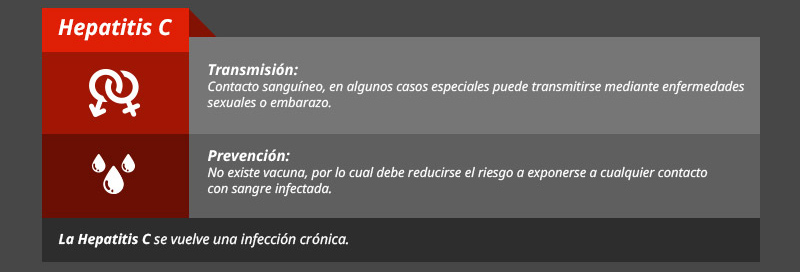

Tipos de hepatitis